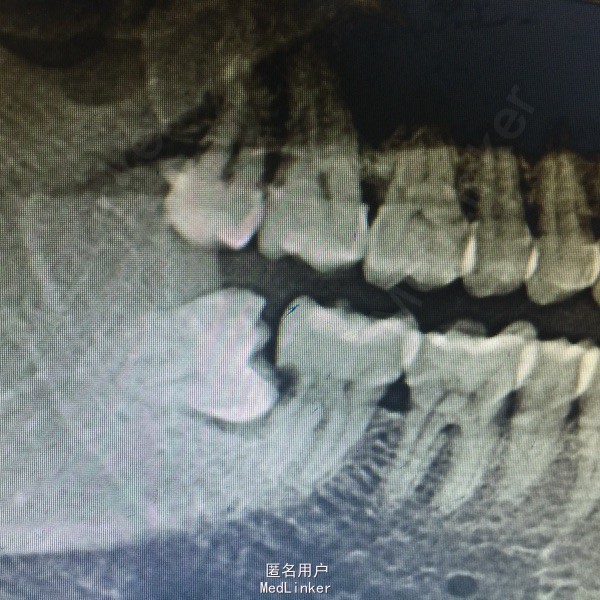

患者男性,40岁,右下后牙肿胀不适数日,近日疼痛加重张口受限,来院就诊。

查体:右面部肿胀,开口型正常,张口受限,48盲袋附着,溢脓,X线示48近中水平阻生,47远中邻面龋坏,龋坏深达牙髓腔。

诊断:48阻生齿,47牙髓炎 处理:48抗炎治疗,炎症控制后拔除48,数日后局麻下,47开髓揭髓顶,拔髓,冲洗进行根管疏通及测量,EDTA机用镍钛器械根管预备,次氯酸钠冲洗,进行热牙胶充填,Zoe暂封观察,建议嵌体修复。